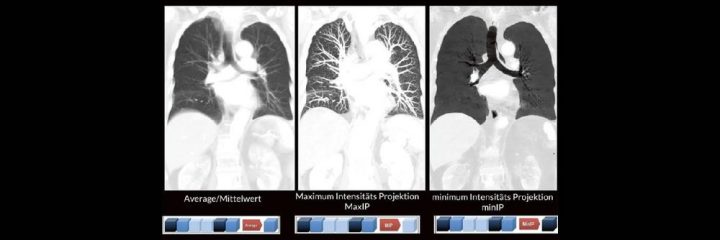

Dr. med. André ReisbergDr. med Sebastian Plößl Die bildgebende HNO-Diagnostik macht es Anfängern nicht leicht. Die Anatomie ist komplex und weniger intuitiv als in anderen Körperregionen. Normvarianten erschweren insbesondere in den Nasennebenhöhlen den Lernprozess. Sobald pathophysiologische Zusammenhänge verstanden und wichtige klinische Aspekte verinnerlicht wurden, gelingt es einen praxistauglichen, belastbaren Befund zu erstellen. Wo muss ich eigentlich hinschauen? Was will der Kliniker von mir wissen und warum? Begleiten Sie uns auf einer kooperativen Reise durch die NNH mit „Ach so!“-Garantie: GemeinsamWeiterlesen